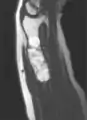

MRI showing enchondromas localized in the lower part of the radius of a 37-year-old patient affected with Ollier disease